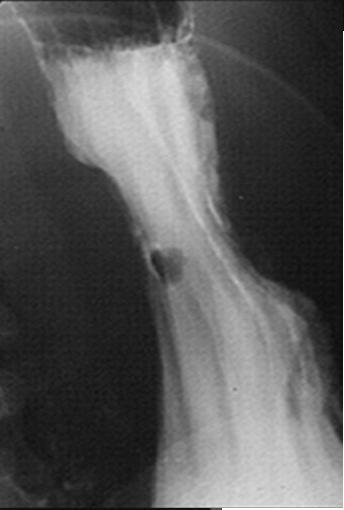

Forme de polyp

du portion verticale de la petit courbure Aspect

de type 1 |